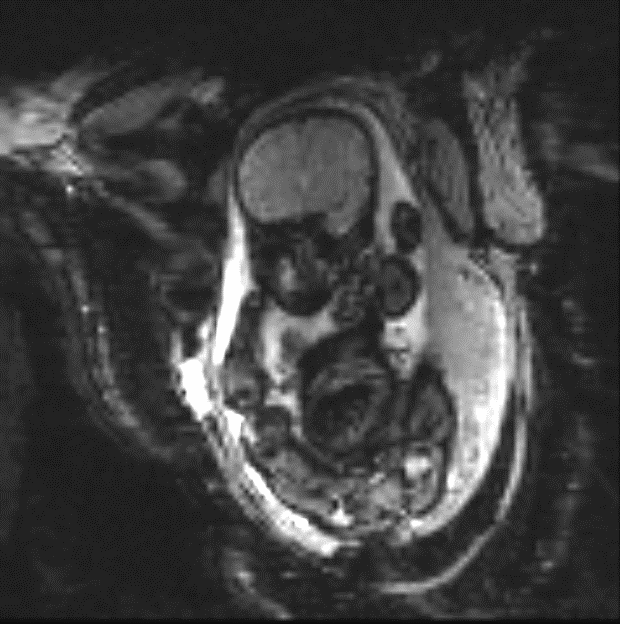

In an ongoing study of placental function by EPI BOLD imaging time series (see Figure 1 (a)), we have built an archive of over 70 subjects, each with 200-500 time frames of EPI volumes, imaged continuously over 10-30 minute observation intervals and resulting in over 18,000 EPI volumes. By visual inspection, the fetal pose can be inferred from these data but manual labeling of keypoints for pose estimation (see Figure 1 (b)) across these volumes is prohibitive and here we propose a method based on deep neural networks to identify fetal key points.

Similar to the task of adult human pose estimation, we model the pose of a fetus with a set of keypoints. We chose fifteen keypoints (ankles, knees, hips, bladder, shoulders, elbows, wrists and eyes) to capture pose and labeled manually, with a representative example shown in Fig. 1(b). These fifteen landmarks were selected as keypoints as they capture gross fetal anatomy that is critical in subsequent motion analysis, and they presented with adequate image contrast to be relatively robustly observed in the MR volumes, thus mitigating the error and noise in labelling. In total, 1705 MR volumes were labelled, 1028() for training, 240() for validation and 437() for testing, where the testing set consists of subjects different from training and validation sets.